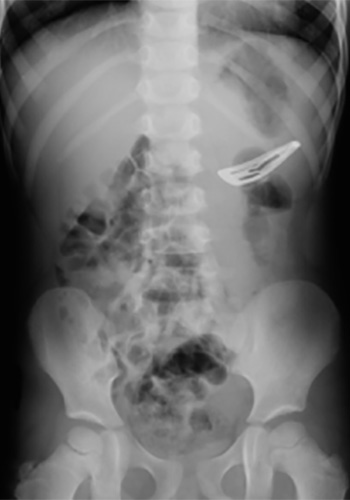

Radiographie du ventre (ASP pour Abdomen Sans Préparation) montrant l’ingestion d’une pince à cheveu chez un enfant :